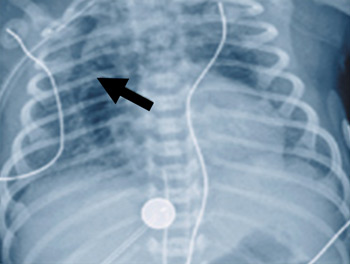

[Figure caption and citation for the preceding image starts]: Pneumomediastino com sinal de "asa de anjo" (seta)Do acervo pessoal do Dr. Vidyasagar e Dr. Bhat [Citation ends].

No pneumomediastino, um sinal de "asa de anjo" (levantamento dos lobos tímicos) na visão posteroanterior é um achado típico.[50]